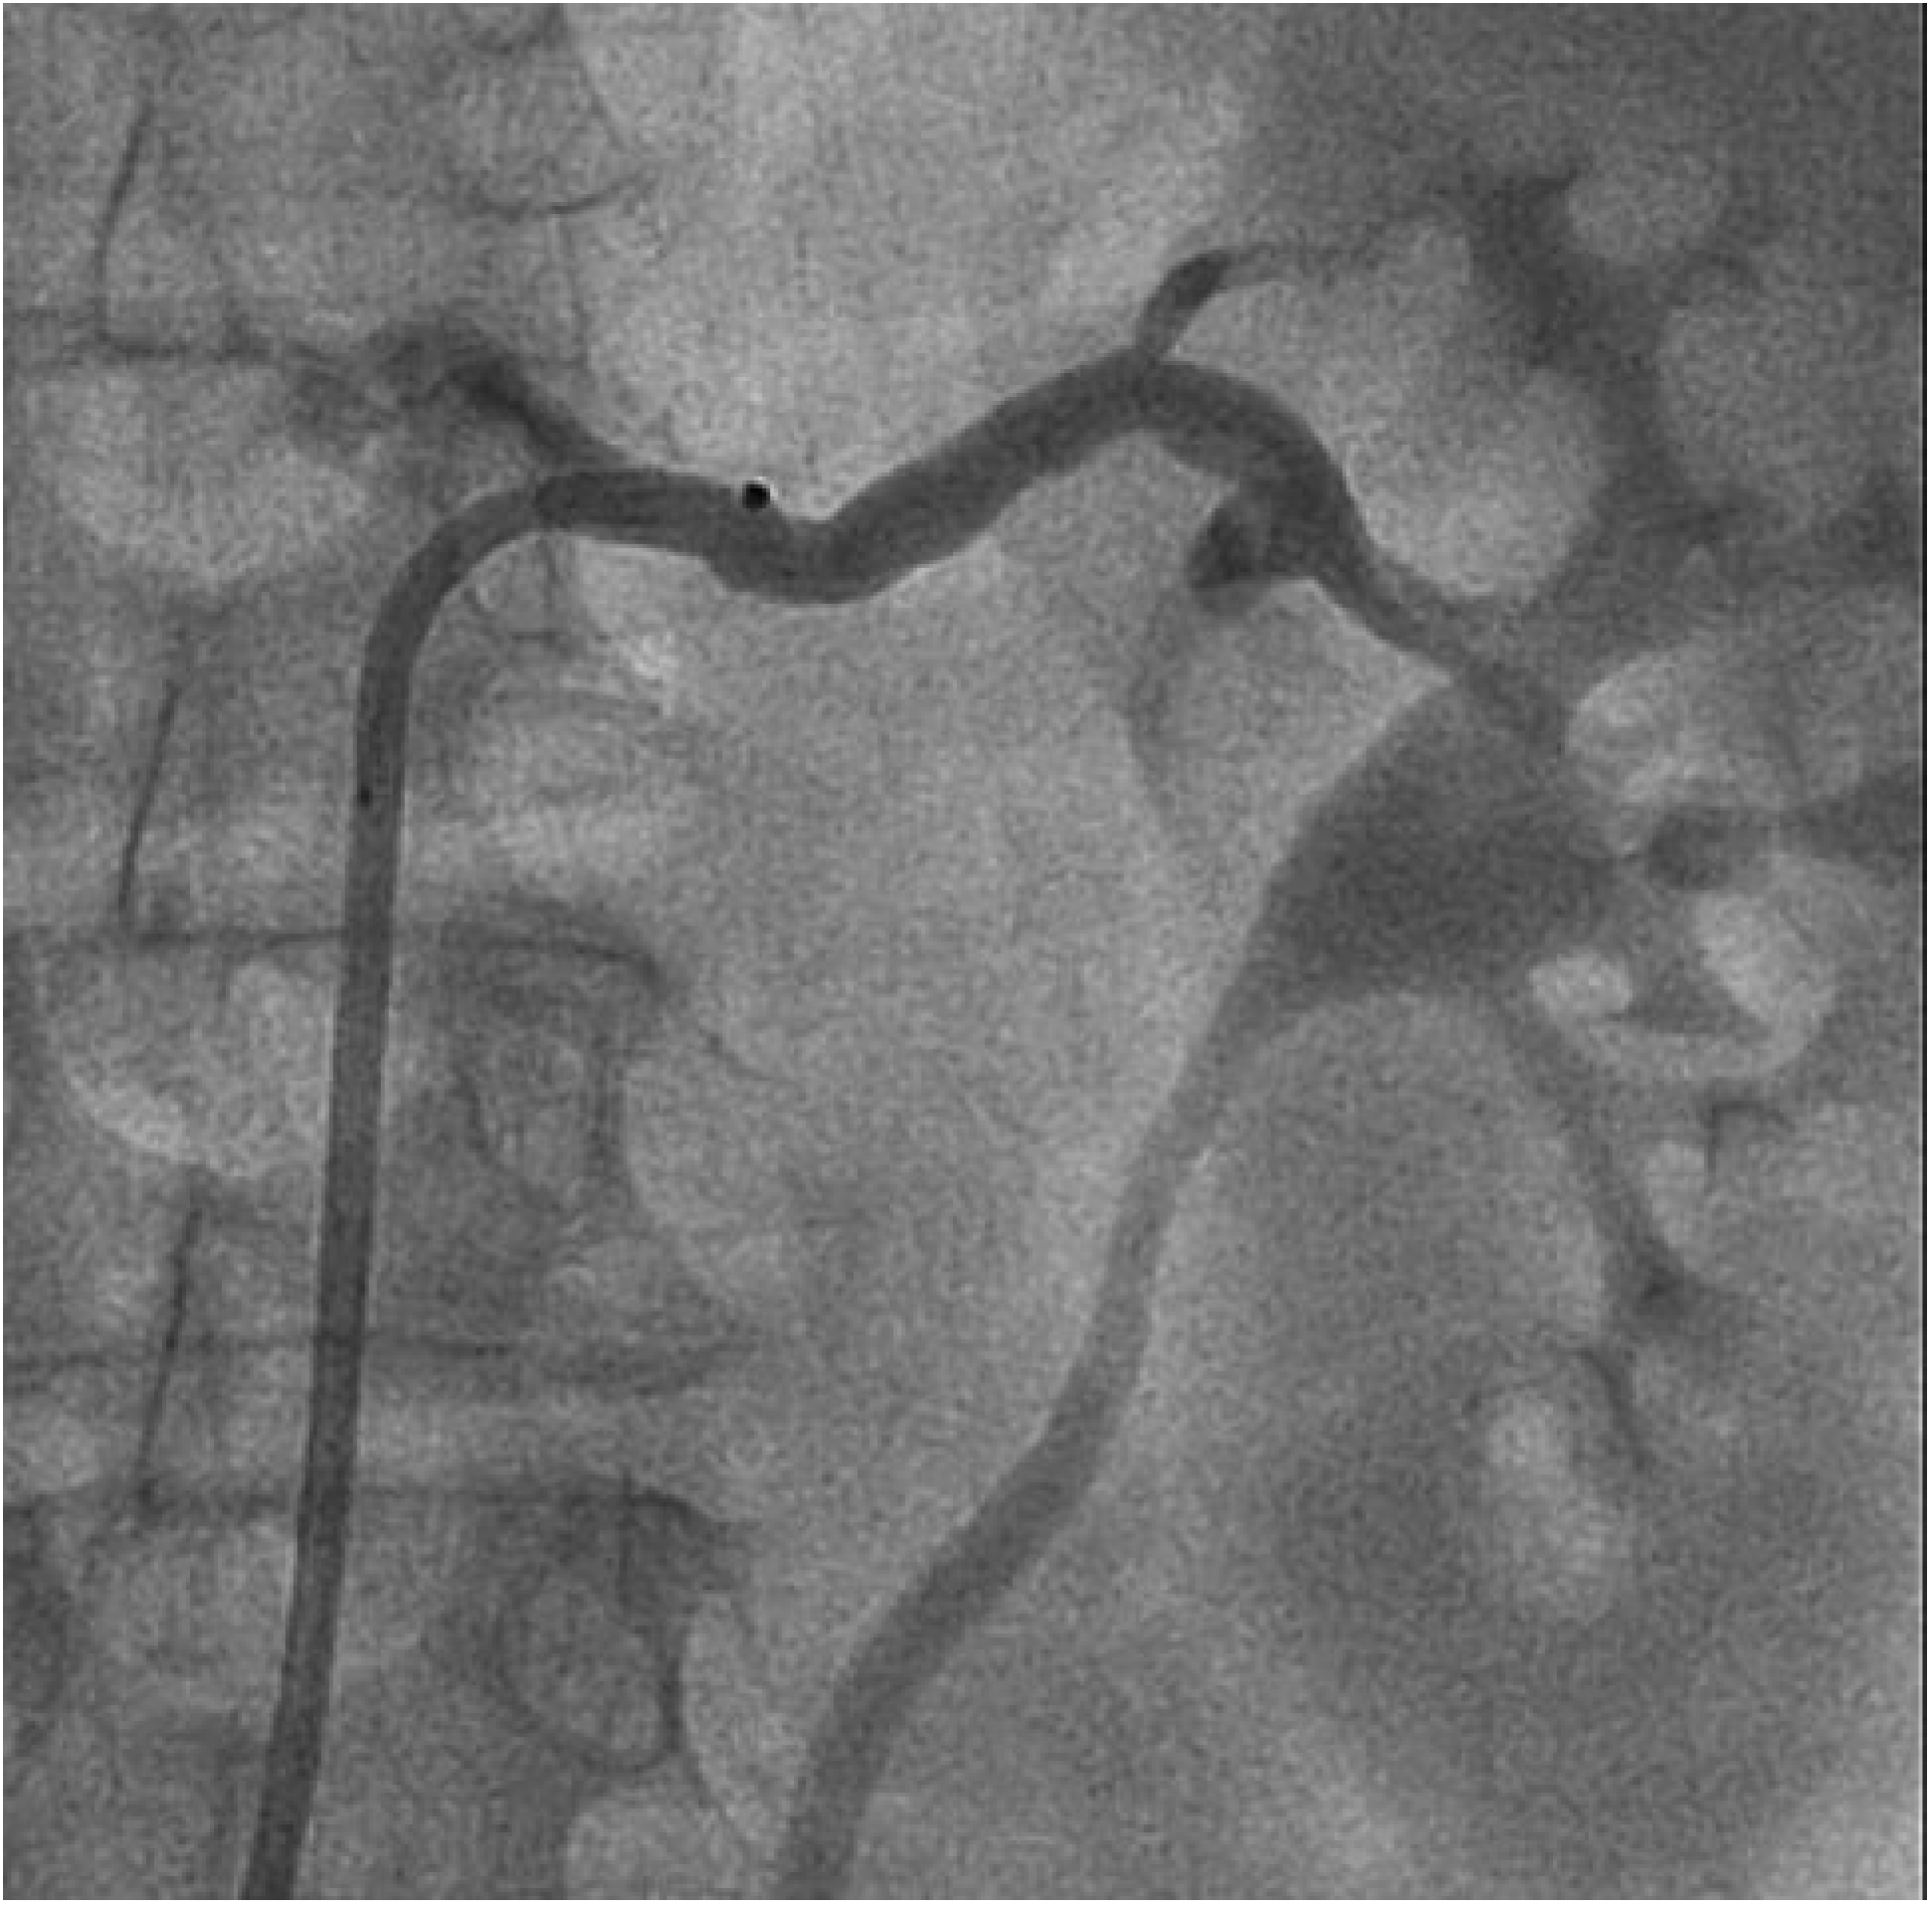

Abbildung 3.

Initiale Darstellung der rechten und linken Nierenarterie zur Überprüfung der Anatomie vor Durchführung der renalen Sympathikusdenervation.

Die Durchführung der renalen Sympathikusdenervation erfolgte im standardmässig eingerichteten Herzkatheterlabor unter monoplaner Durchleuchtung. Die Vorbereitung der Patientin entsprach im Wesentlichen der einer Koronarangiographie. Nach lokaler Anästhesie der vorgesehenen Punktionsstelle erfolgte die Punktion der linken Arteria femoralis. Mittels Seldinger-Technik wurde eine 8-French-Schleuse in das Gefäss eingeführt. Anschliessend erfolgte nochmals die Darstellung der renalen Gefässanatomie (Abb. 3). Es zeigte sich entsprechend dem magnetresonanztomographischen Vorbefund eine geeignete Anatomie beider Nierenarterien. Nun wurde ein 8-French-LIMA-Führungskatheter eingebracht und die linke Nierenarterie intubiert. Über einen Führungsdraht (BMW, Abbott Laboratories, Illinois, USA) wurde in der Folge ein 5-F-Multipurpose-Katheter bis zur Bifurkation der Nierenarterie eingeführt. Nach Rückzug des Führungsdrahtes wurde über den liegenden 5-F-Katheter der Symplicity™-Ablationskatheter in der linken Nierenarterie platziert. Danach wurde der 5-F-Katheter zurückgezogen und ein Kontakt der Spitze des Ablationskatheters mit der Nierenarterienwand hergestellt (Abb. 4).